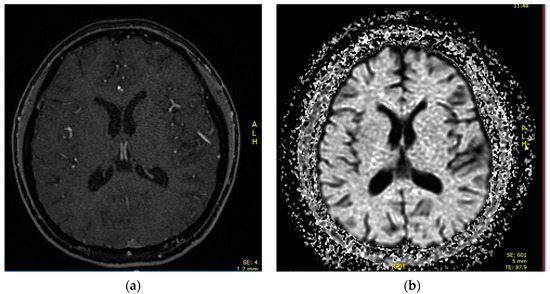

2.2. Case 2